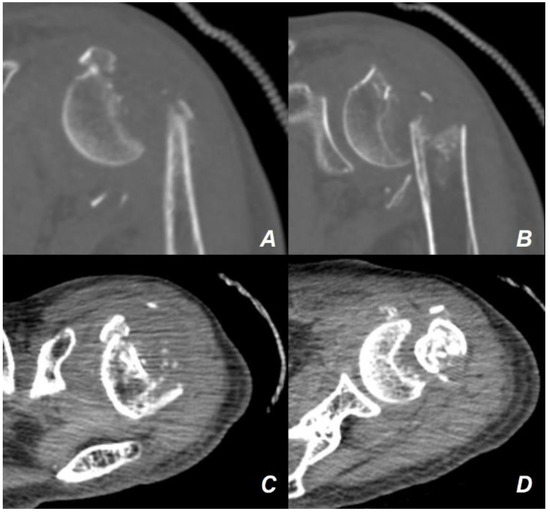

2. Case Presentation

Surgical Technique